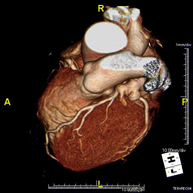

El angio-TC Cardíaco o Coronariografía no invasiva es una prueba diagnóstica que consiste en el estudio de las arterias del corazón o arterias coronarias mediante el empleo de un equipo de TC Multidetector de última generación y de un contraste yodado, obteniendo imágenes bi y tridimensionales. El TC Multidetector o TCMD permite una adquisición de imágenes tan rápida, que se pueden valorar las arterias coronarias con una alta precisión anatómica: estrechamientos o estenosis, calcificaciones, variantes anatómicas, etc., ya que gracias a su rapidez evita el artefacto que provoca el movimiento constante del corazón (tarda menos de diez segundos en adquirir unas 1000 imágenes). La información obtenida precisa de un tratamiento en estaciones de trabajo con programas especializados en la reconstrucción de las arterias coronarias que permiten valorar el número, la localización y las características de las lesiones. Toda esta información se obtiene de manera no invasiva: solo se requiere la punción de una vena periférica (en el brazo). Es necesario que la frecuencia cardíaca no supere los 75 latidos por minuto, por lo que algunos pacientes deberán realizar un tratamiento previo con un fármaco betabloqueante. - PAAF (Punción) Tórax guiada por TC

L'Angio TC cardíac o la coronariografia no invasiva és una prova diagnòstica que consisteix en l'estudi de les artèries del cor o artèries coronàries mitjançant l'ús d'un equip de TC Multidetector d'última generació (64 corones o files de detectors) i de contrast iodat amb l'obtenció d'imatges bi i tridimensionals. El TC Multidetector 64 o TCMD64 permet una adquisició d'imatges tan ràpida que es poden valorar les artèries coronàries amb alta precisió anatòmica (estrenyiments o estenosis, calcificacions, variants anatòmiques, etc.), ja que, gràcies a la seva rapidesa, evita les falses imatges que provoca el moviment constant del cor (triga menys de deu segons en adquirir unes 1000 imatges). La informació obtinguda d'un tractament en estacions de treball amb programes especialitzats en la reconstrucció de les artèries coronàries que permeten valorar el nombre, la localització i les característiques de les lesions. Tota aquesta informació s'obté de manera no invasiva: només es necessita la punció d'una vena perifèrica (en el braç). És necessari que la freqüència cardíaca no superi els 75 batecs per minut, per això els pacients han de realitzar un tractament previ amb un fàrmac betabloquejant. - Angio TC d'aorta abdominal